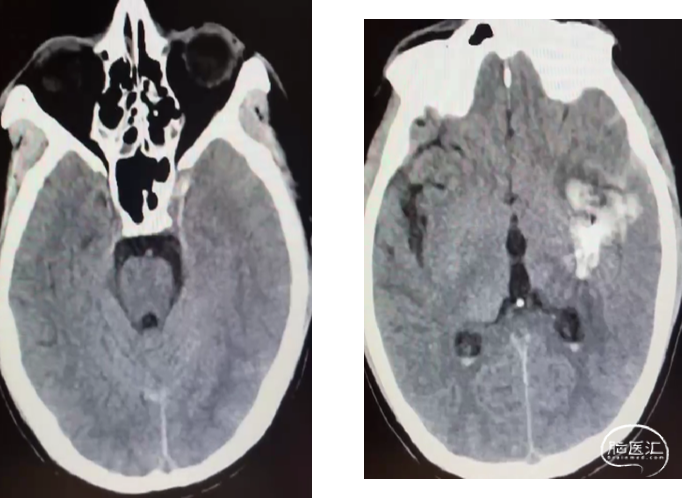

术中动脉造影

动静脉联合3d显示引流静脉与矢状窦关系;中天21微导管塑形(半圆)支撑下FATHOM-14导丝超选成功,考虑enchlon10长度不够,截断中管;FATHOM-14 3m交换enchelon10,但阻力大未能到位,中间管也未能到引流静脉入口;头羊作用下apollo3cm超选到位。

球囊保护静脉入路栓塞:注射onyx34约1ml,onyx18约1.5ml,总时长20min。

术后即刻造影畸形血管团不显影